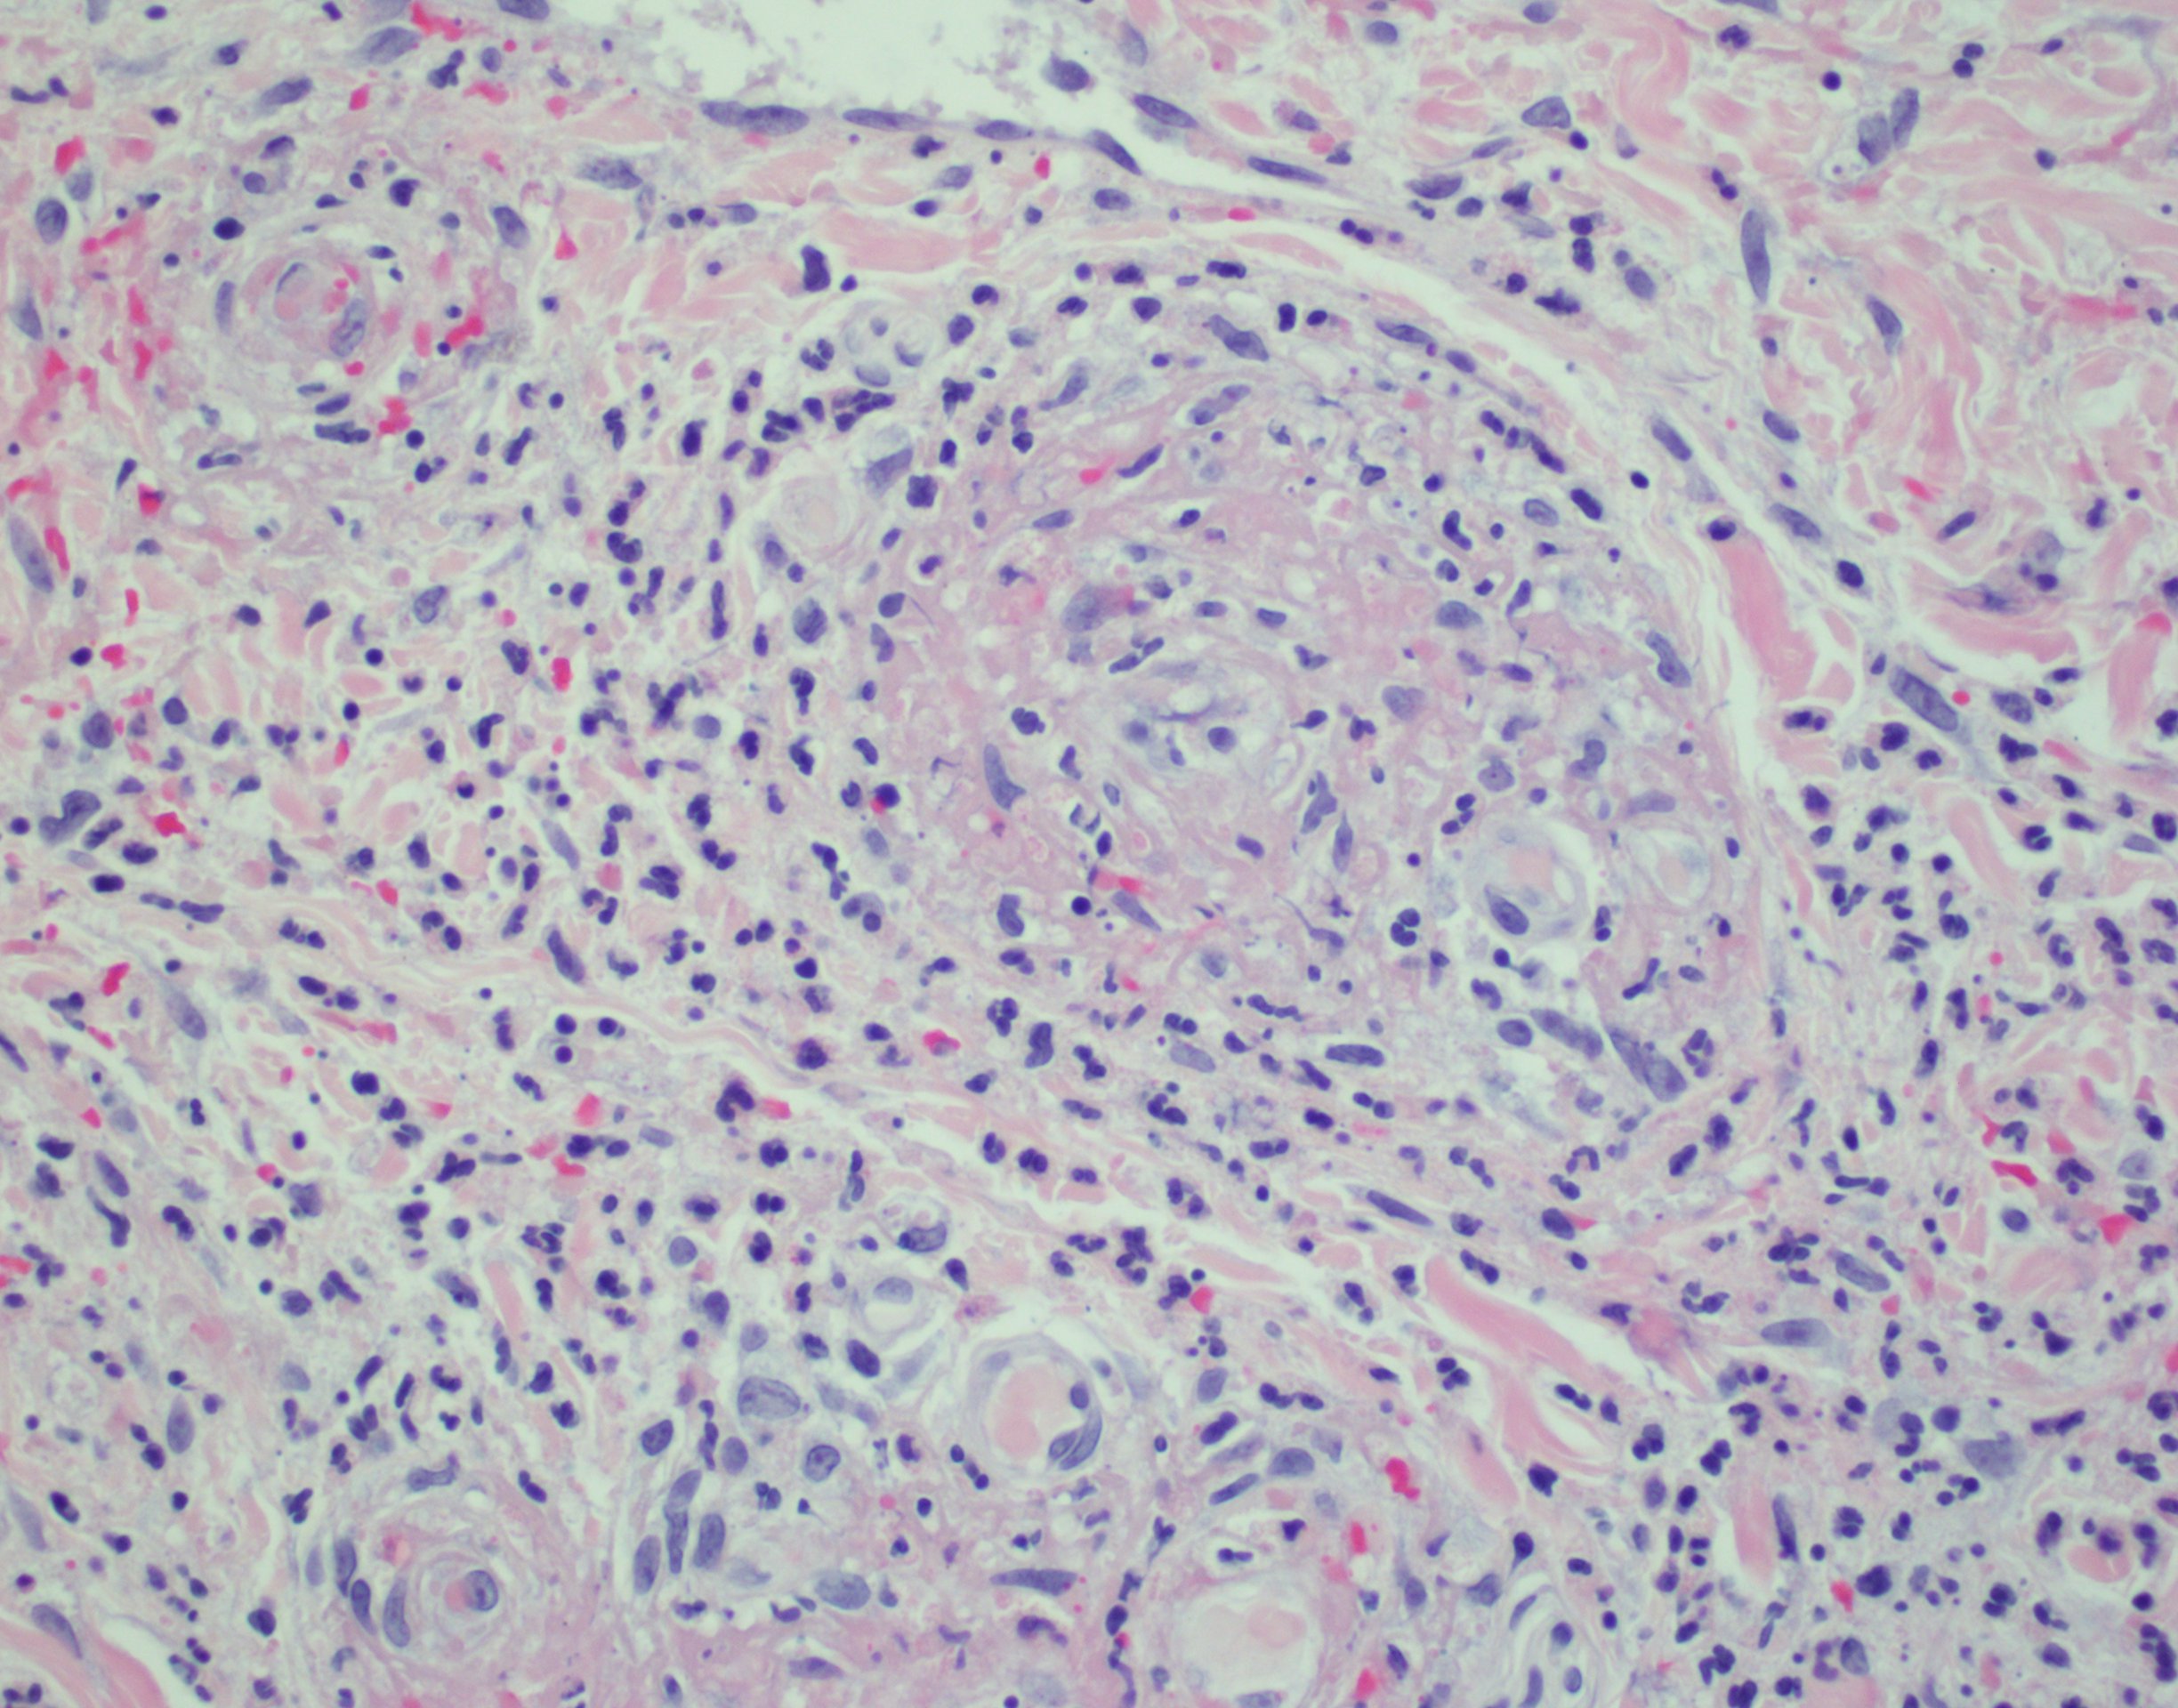

The rapid development of coalescing palpable purpura, acute kidney injury, and joint arthralgias subsequent to initiating a new medication strongly suggests a hypersensitivity vasculitis.1 Histopathologic study revealed neutrophilic vasculitis with red blood cell extravasation, perivascular and interstitial neutrophils, nuclear dust, and vascular damage with fibrin deposition (Figures 2-4). Under direct immunofluorescence, deposition of immunoglobulin G, immunoglobulin A, C3, immunoglobulin M, and fibrin were observed in the blood vessels and vessel walls. These findings confirmed the diagnosis of LCV.2

Figure 4. Section from a punch biopsy of skin lesions demonstrating neutrophilic vasculitis with erythrocyte extravasation, perivascular and interstitial neutrophils, nuclear dust, and vascular damage with fibrin deposition (hematoxylin-eosin; ×400 magnification).Fluoroquinolones are among the drugs known to induce vasculitis.3 Medication use also accounts for most cases of SJS and DRESS.4,5 However, SJS is more commonly associated with epidermal necrosis and involvement of 2 or more mucosal sites.4 DRESS usually appears several weeks after the first introduction of an offending medication.5 Eosinophilic granulomatosis with polyangiitis may present with cutaneous vasculitis and renal damage; lack of infiltrating eosinophils on skin biopsy demotes this diagnosis.6